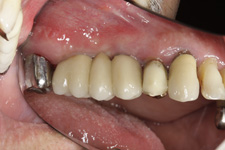

V případě chybění většího počtu zubů v postranních úsecích čelistí je možné ošetření pomocí implantátů, které nahradí ošetření pomocí snímacích náhrad kotvených na zbývajících zubech nebo patře.

Podmínkou je opět dostatečné množství kosti.

Protetické řešení může být pomocí můstku, který je kotvený na implantátech nebo pomocí jednotlivých korunek na implantátech.

V zásadě je možné do těchto můstků zařadit i přirozené zuby, zejména pokud je potřeba tyto zuby ošetřit proteticky – korunkami. Korunky nebo můstky mohou být na implantáty nacementovány nebo přišroubovány.

Zdravé zuby zůstanou zachovány a přitom náhrady jsou pevné, jako na vlastních zubech